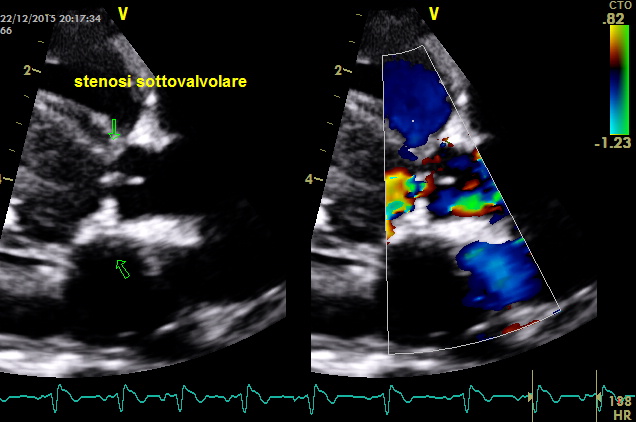

come si puo’ notare dai particolari nelle immagini zoom la struttura valvolare appare integra con una normale conformazione delle cuspidi la turbolenza e’ generata da una piccola banda fibrosa sottovalvolare ,in questo caso a dispetto delle alterazioni minime visualizzabili nell’esame B mode la stenosi sulla base del gradiente appare severa ,il PHT inferiore ai 300mm/sec dell’insufficienza aortica che quasi sempre accompagna la stenosi indica pressioni diastoliche nel ventricolo sx elevate

I difetti possono coesistere in questo caso la polmonare e’ normale ,nei primi video si ha la sensazione che coesista un DIV (flusso in avvicinamento concomitante la sistole tuttavia le differenze di gradiente sono troppo elevate tra camera destra e sx dovrebbe generarsi turbolenza che non si vede ,il soggetto deve essere comunque ricontrollato .